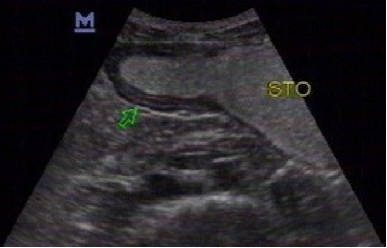

超声图像,箭头所指,低回声结节,无蒂,呈丘状,表面光滑,起源于粘膜层。

胃造影用的是什么机子胃肠超声造影--无创、无痛、无辐射!_https://www.jmylbn.com_新闻资讯_第12张

胃镜取材活检,病理证实为增生性息肉。